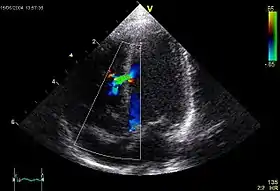

A VSD can be detected by cardiac auscultation. Classically, a VSD causes a pathognomonic holo- or pansystolic murmur. Auscultation is generally considered sufficient for detecting a significant VSD. The murmur depends on the abnormal flow of blood from the left ventricle, through the VSD, to the right ventricle. If there is not much difference in pressure between the left and right ventricles, then the flow of blood through the VSD will not be very great and the VSD may be silent. This situation occurs a) in the fetus (when the right and left ventricular pressures are essentially equal), b) for a short time after birth (before the right ventricular pressure has decreased), and c) as a late complication of unrepaired VSD. Confirmation of cardiac auscultation can be obtained by non-invasive cardiac ultrasound (echocardiography). To more accurately measure ventricular pressures, cardiac catheterization, can be performed.

h) Intraoperative transesophageal echocardiography is used to confirm secure closure of the VSD, normal function of the aortic and tricuspid valves, good ventricular function, and the elimination of all air from the left side of the heart.